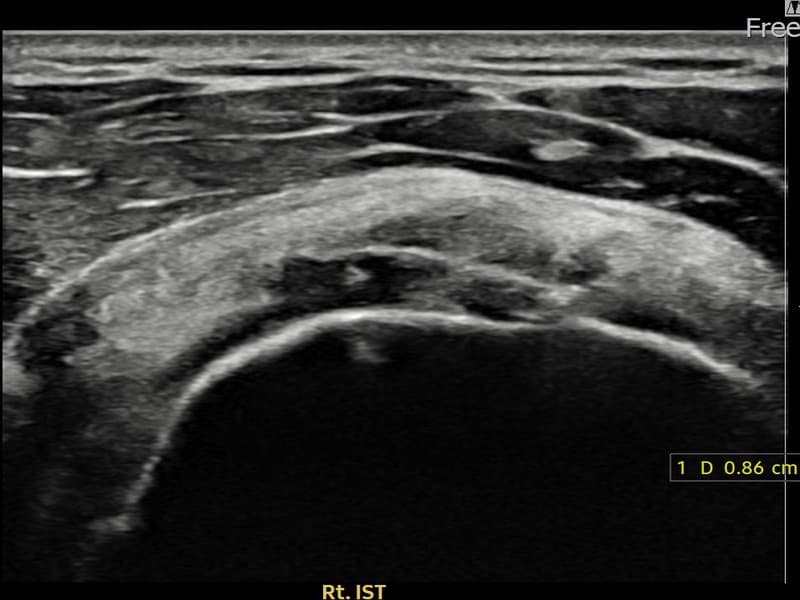

超声确认右侧 冈下肌腱 关节面侧部分撕裂(7mm × 3mm (肌腱厚度约32%缺损))。缩小缝合术后肌腱连续性恢复,患者回归正常生活。

术前超声确认右侧 冈下肌腱 关节面侧部分撕裂,右侧冈下肌腱回声不连续伴肌腱缺损(7mm × 3mm (肌腱厚度约32%缺损))。术后超声显示撕裂部位充满再生组织,肌腱连续性恢复,回声模式正常化。

该患者持续肩痛。详细超声检查确认右侧 冈下肌腱 关节面侧部分撕裂(缺损:7mm × 3mm (肌腱厚度约32%缺损))。在超声引导下实施非手术缩小缝合术。术后佩戴支具约4-6周,随后进行分阶段康复锻炼。随访超声确认肌腱连续性恢复、结构稳定,患者顺利回归日常生活。